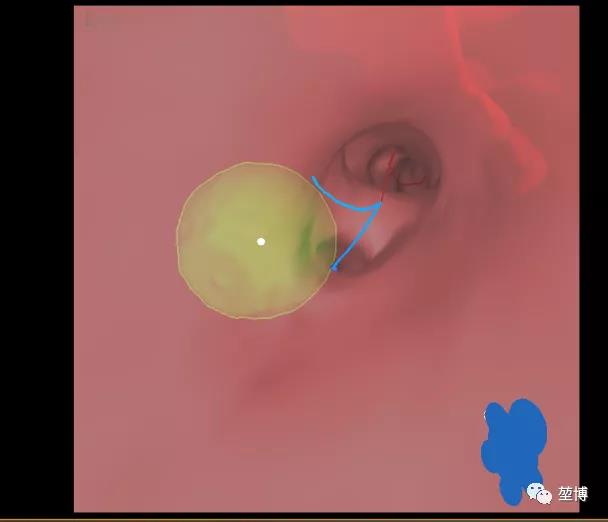

如上图所示,该患者病灶有明显气道相通,但气道紧挨病灶边缘,单纯气道内消融无法抵达病灶中央,达到最大的消融治疗效果,因此选择内外结合法——气道内消融+气道外消融。拟在LungPro导航引导下行BTPNA术,直接抵达病灶中心,随后进行气道外消融。

气道内消融预测范围

气道外消融预测范围